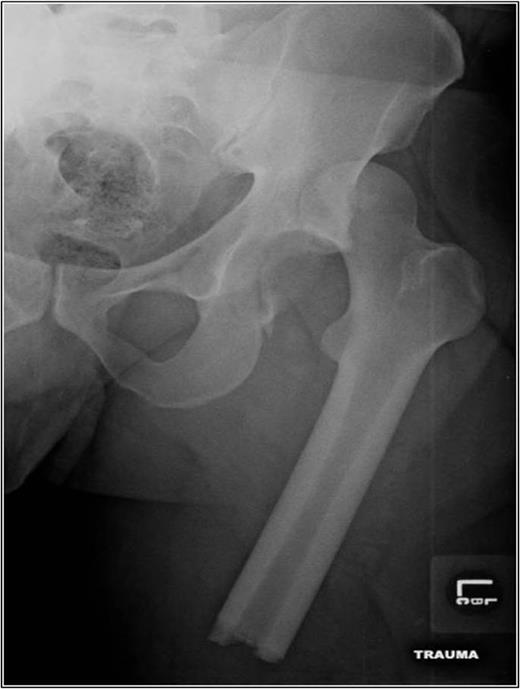

A 35-year-old male was involved in a high-speed urban dirt biking accident. The patient was stable with a GCS of 15 and was neurovascularly intact. His left knee exhibited a 10 × 20 cm medial traumatic arthrotomy and his thigh compartments were soft and compressible. Imaging revealed a left hip postero-superior dislocation, posterior wall acetabular fracture, ipsilateral transverse femoral diaphyseal fracture and an engaging hill-sachs-type lesion of the femoral head with the postero-superior acetabulum (Figs 1–3). Cefazolin, gentamicin and tetanus prophylaxis were administered along with a bedside washout of the traumatic arthrotomy. The patient was medically cleared for operative intervention as all blood work and further imaging were normal.

AP left hip demonstrating a diaphyseal transverse femur fracture with ipsilateral hip dislocation.